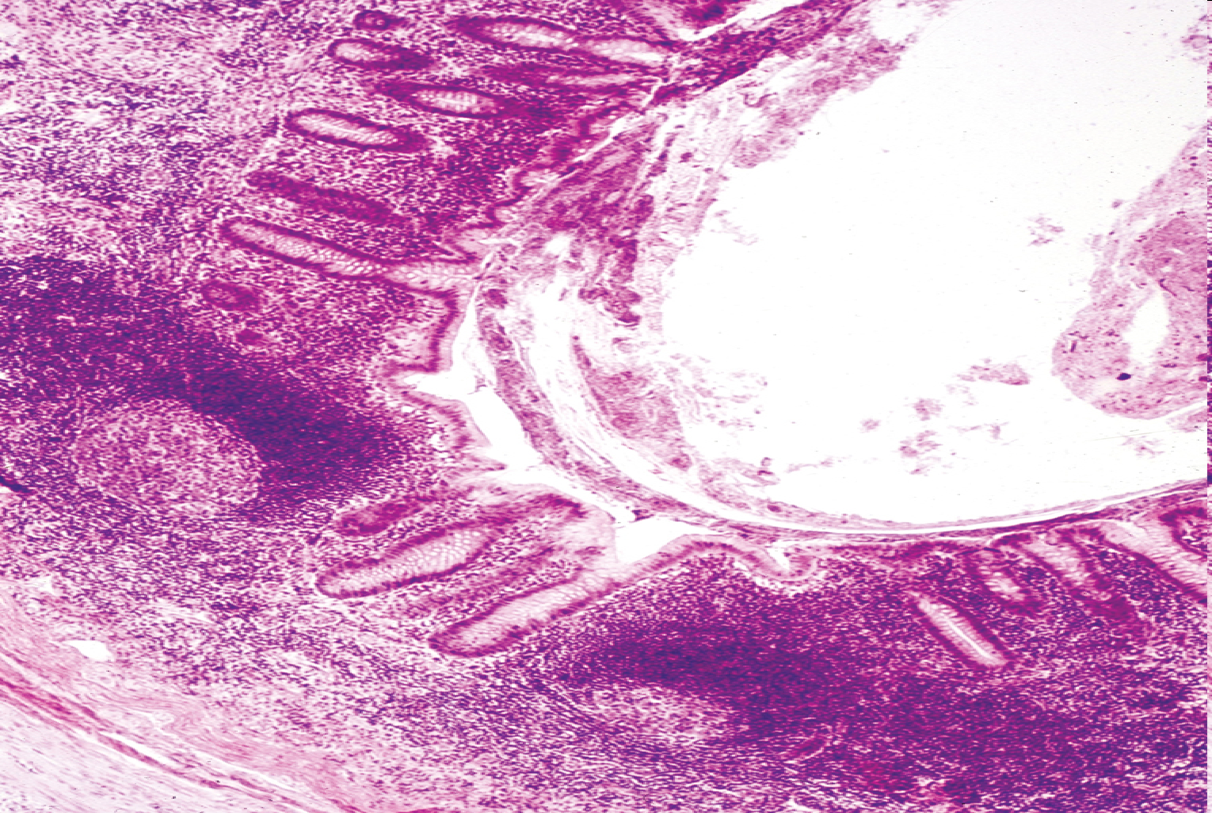

What is this?

Appendix. has a very small lumen, fewer glands in its mucosa, and no taeniae coli. The laminar propria and submucosa are generally filled with lymphocytes and lymphoid follicles, making the appendix a significant part of the GALT